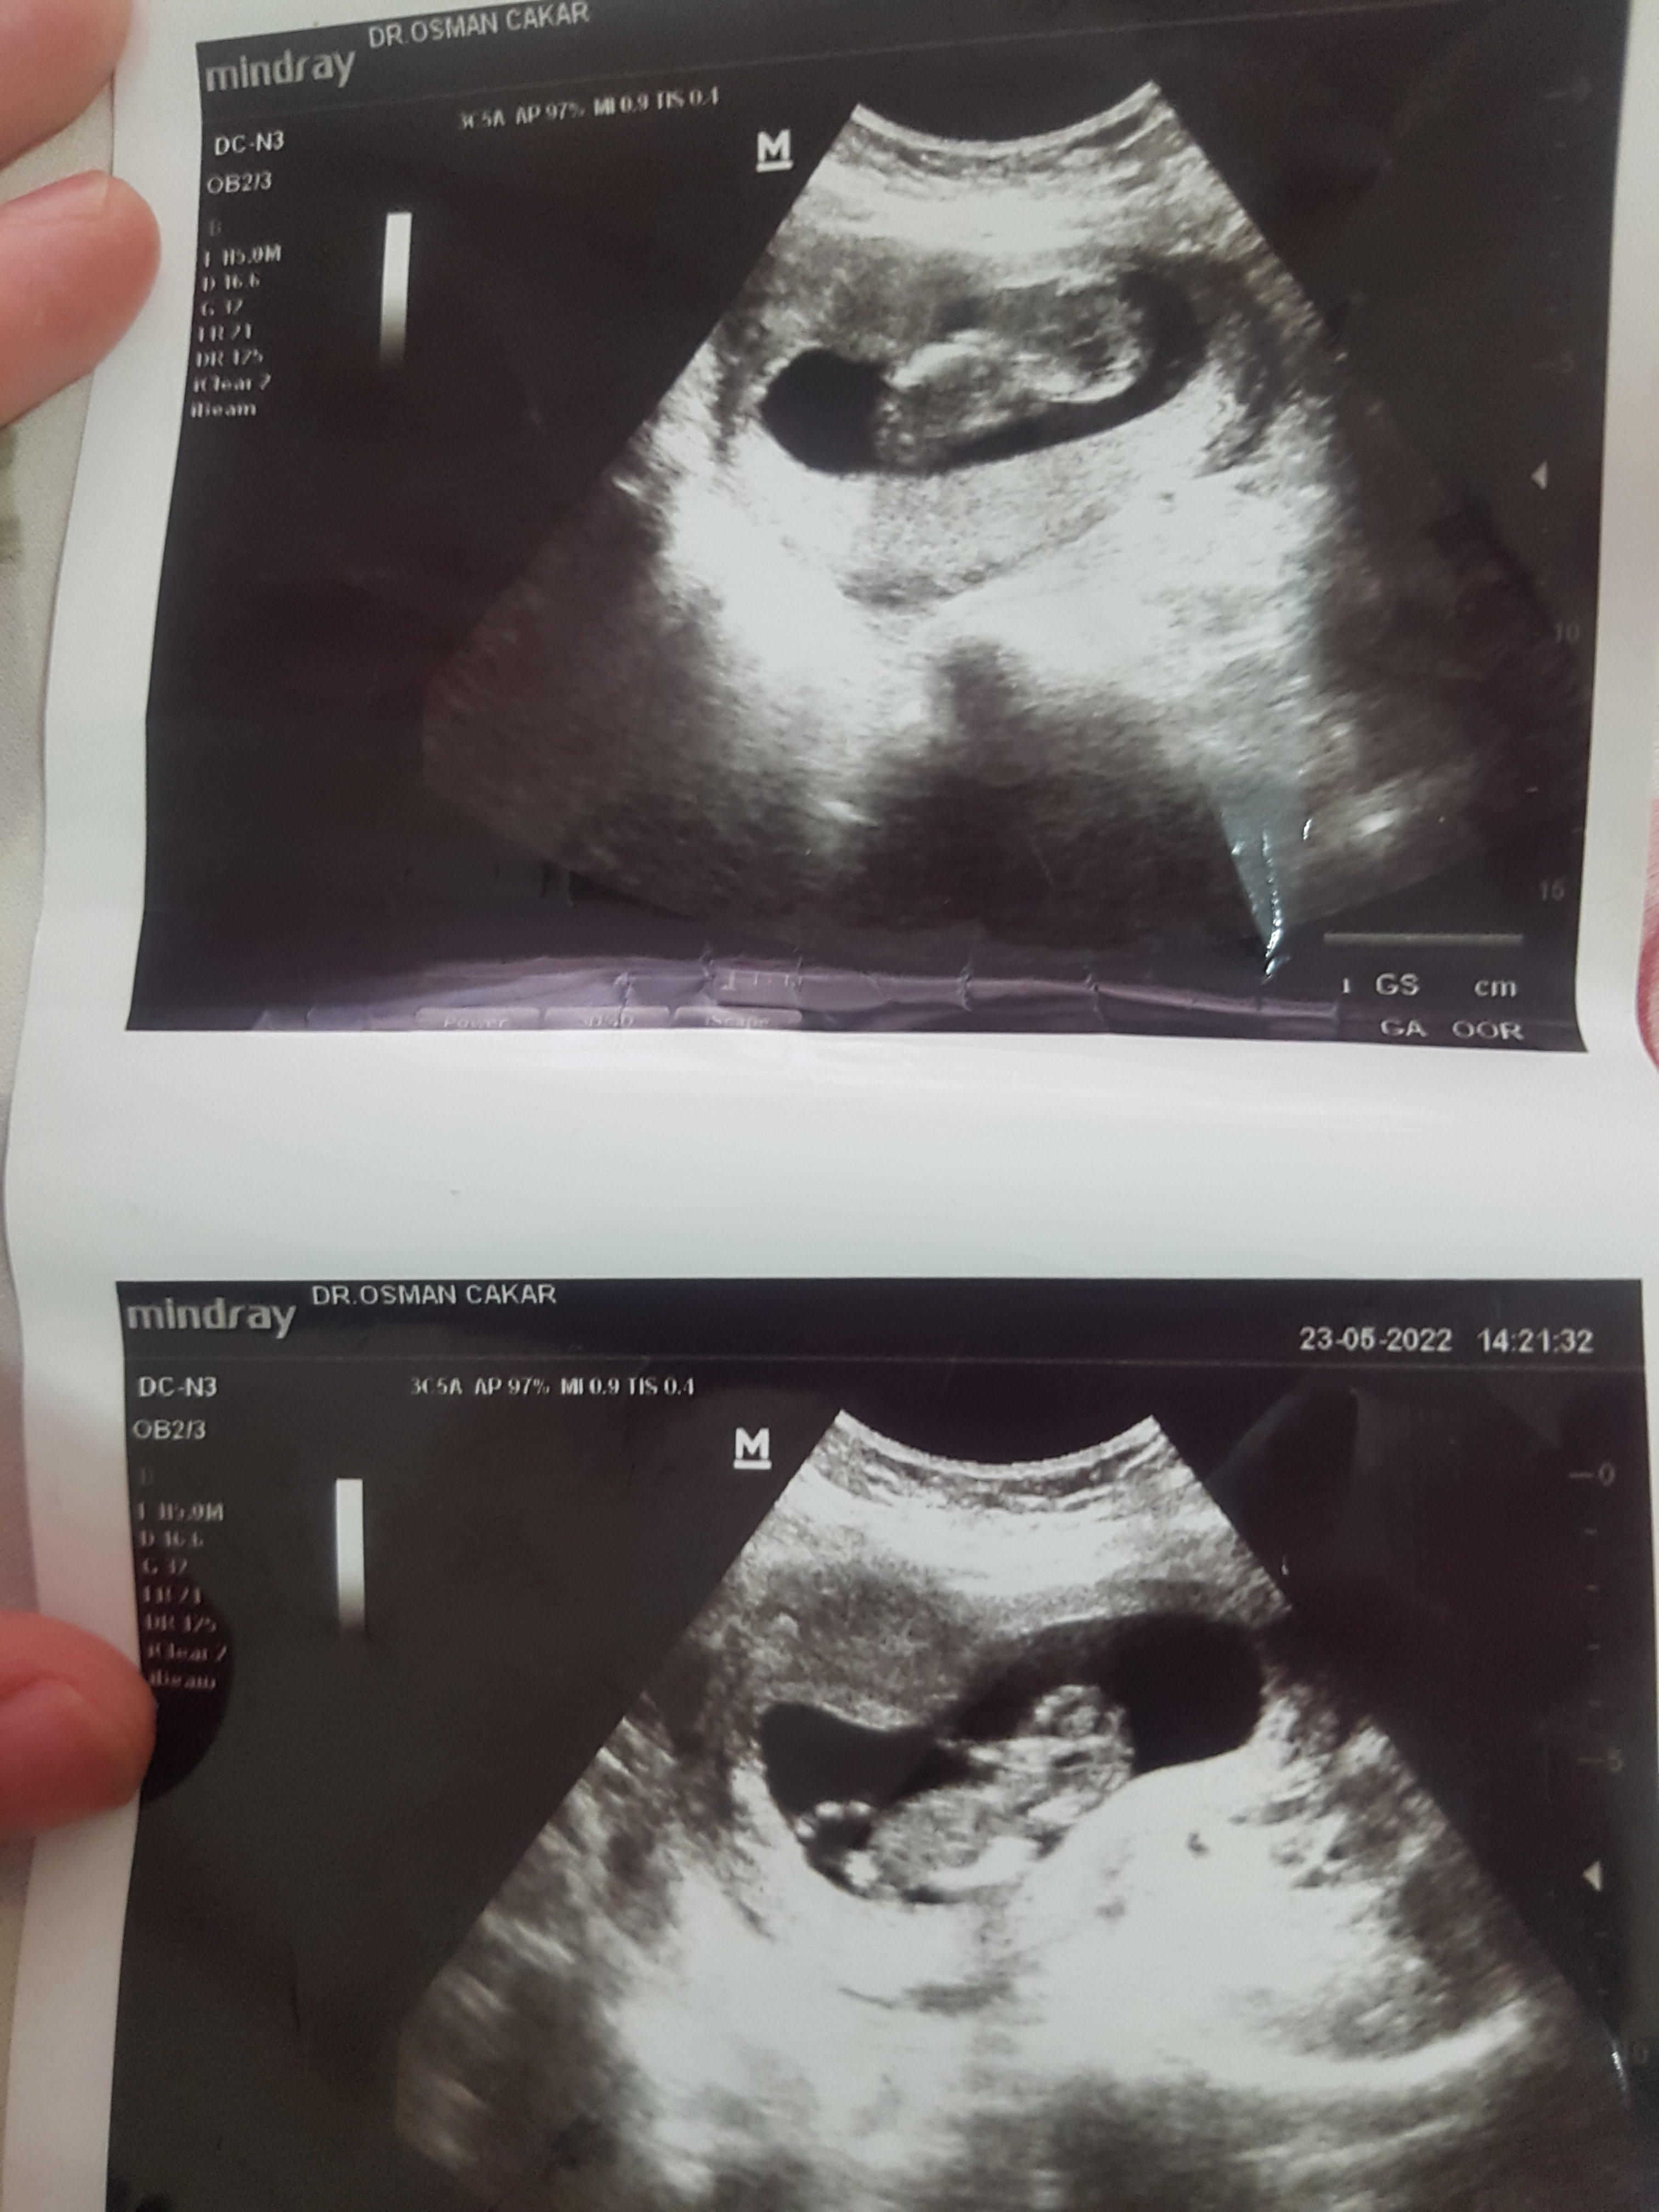

Ekli dosyayı görüntüle 2097

Kızlar bugün hastaneye gittim doktor ikizlerin olacak dedi vok şaşırdım bundan önce 3 defa hastaneye gittim kimse ikiz olduğunu söylemedi hem vok mutlu hem çok şaşkınım